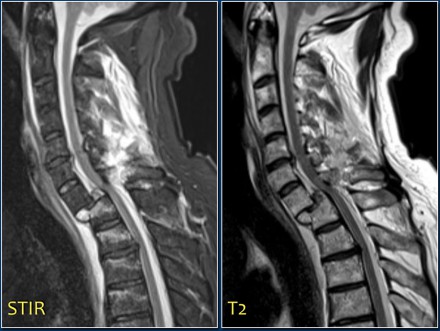

Continue with the MRI-images.

Again look at the first MR-images and decide what is going on.

Then scroll to the next images.

The findings are:

- Anterior displacement of C7 to Th1.

- Protrusion of the disc.

- Compression of the spinal cord.

- Bone marrow edema in several vertebral bodies, either due to contusion or fracture.

- Interspinous edema and disruption of the ligamenta flava C7-Th1 and supraspinous ligament Th1-Th2.